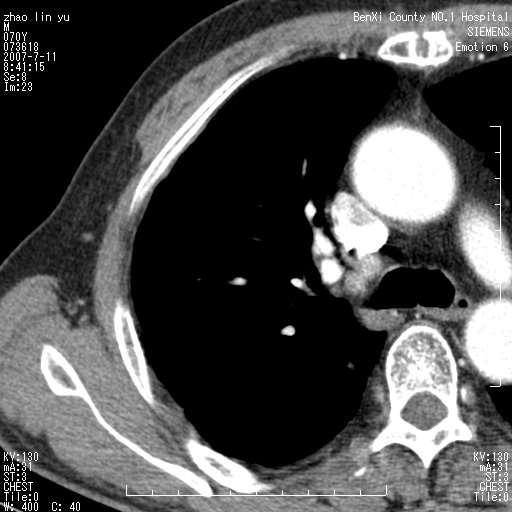

以下是引用王靖旗在2007-7-10 17:12:00的发言:[br] 男、70、咳嗽两个月,半年前换瓣手术,胸片未见异常,于昨天行x片发现右肺上野大片影,行ct扫描,这里是减薄图像,余肺正常。明天晚上会有增强扫描片,到时我会上传。[br][br] 冠状位请大家细看,应该是有意义的,[br][br] 请大家先看平扫发表意见。[br][br]

以下是引用zhangzhongshou在2007-7-10 21:43:00的发言:[br]右肺上叶周围型肺癌,以孤立型细支气管肺泡癌可能性大。